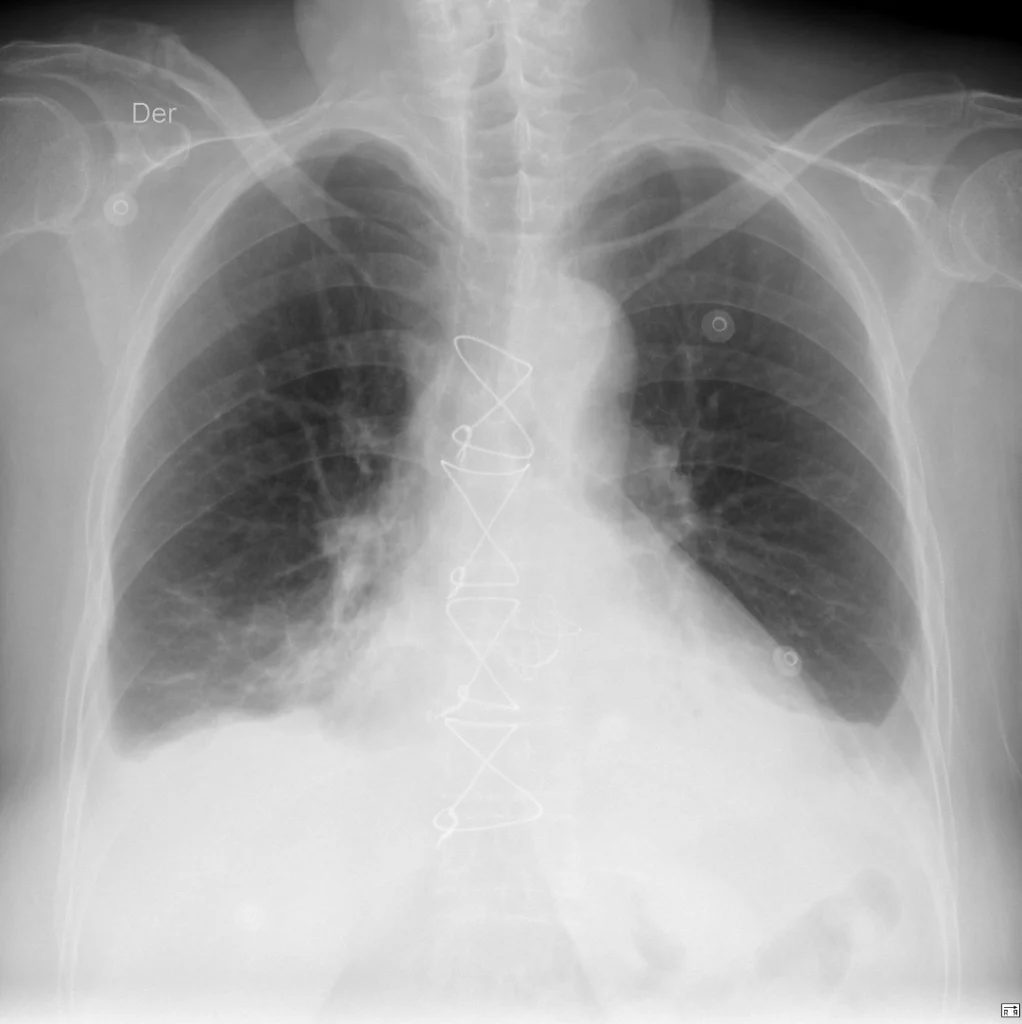

Rx de tórax PA. Los SCF laterales han perdido su aspecto en ángulo agudo habitual están ocupados por material radiopaco (trasudado). A la derecha el SCF se observa obtuso, pero a la izquierda, una curva de concavidad superior delimita el derrame pleural (signo del menisco). Otros hallazgos: sutura metálica esternal; válvula aórtica protésica; aumento del ICT.

La proyección PA de la radiografía de tórax se realiza con el paciente de pie. Por efecto de la gravedad, el material qué ocupa la cavidad pleural (en este caso trasudado – derrame pleural) ocupa inicialmente las zonas más declives. En la proyección PA, el primer signo es la ocupación de los senos costofrénicos (SCF) laterales. Cuándo el volumen del derrame crece, encontramos otro signo radiológico: el “signo del menisco”. Se observa como un borde en forma de “U” a medida que el líquido se eleva a lo largo de la pared lateral del tórax.

Los SCF laterales pueden seguir siendo agudos sí el derrame pleural es de pequeño volumen (menos de 200 cc). Si la sospecha es alta, evalúa en la proyección lateral los SCF posteriores. Recuerda que anatómicamente, estas son realmente las áreas más declives de los pulmones y del espacio pleural.